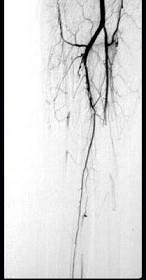

问题 43岁女性患者,突发左手疼痛伴多个指头麻木就诊,行左上肢动脉照影,示左侧桡动脉广泛的充盈缺损,结合临床考虑左侧桡动脉病变为 ( )

选项 A、桡动脉血栓形成 B、桡动脉假性动脉瘤 C、桡动脉炎 D、桡动脉真性动脉瘤 E、桡动脉夹层

答案 A